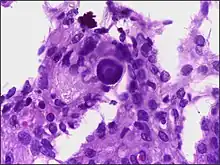

Although the majority of meningiomata are benign, they may have malignant presentations. Classification of meningiomata are based upon the WHO classification system.[19]

- Benign (Grade I) – (90%) – meningothelial, fibrous, transitional, psammomatous, angioblastic

- Atypical (Grade II) – (7%) – chordoid, clear cell, atypical (includes brain invasion)

- Anaplastic/malignant (Grade III) – (2%) – papillary, rhabdoid, anaplastic (most aggressive)